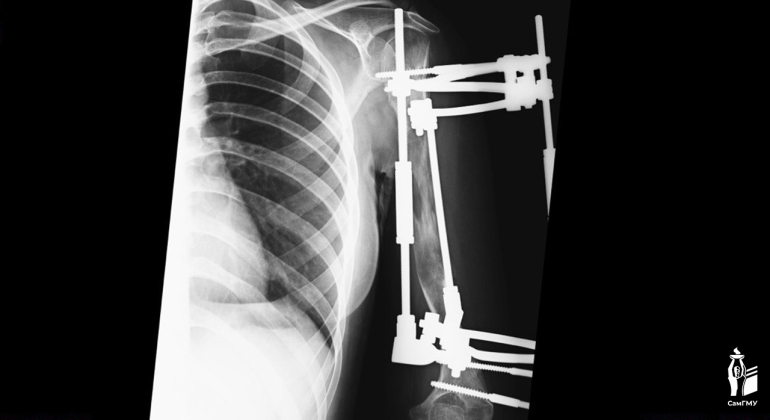

Пациентке поэтапно вырастили свою собственную кость.

В Самарской области хирурги провели уникальную операцию. В клинике СамГМУ врачи удлинили руку девушки на 13 сантиметров.

В раннем возрасте пациентку настигла тяжелая болезнь. Острый гематогенный остеомиелит разрушил зону роста в верхней части плеча, из-за чего разница между руками достигла 15 сантиметров. Это не только вызывало косметический дискомфорт, но и ограничивало выполнение простых повседневных задач. Медики решили удлинить руку.

- Удлинение верхней конечности на такую большую величину за одну операцию — смелое решение, мы понимали, что есть риски осложнений. Для удлинения на такую большую величину подходит метод Илизарова, при котором поэтапно выращивается своя собственная кость, - пояснил врач Никита Лихолатов.

Как пояснил медик, обычно такое растяжение у детей проводится на 1 мм в сутки. Костные фрагменты раздвигаются, между ними образуется мягкая костная мозоль, которая в дальнейшем перестраивается в кость. Но так как девочке было уже 17 лет, процесс растяжение проходил медленнее обычного - менее 1 мм в сутки, чтобы избежать повреждения мягких тканей.

Пациентка носила аппарат долгое время, могла учиться и заниматься повседневными делами. Недавно аппарат сняли, и теперь она проходит реабилитацию. Врачи успешно устранили косметический дефект и восстановили функциональность руки.

фото: СамГМУ